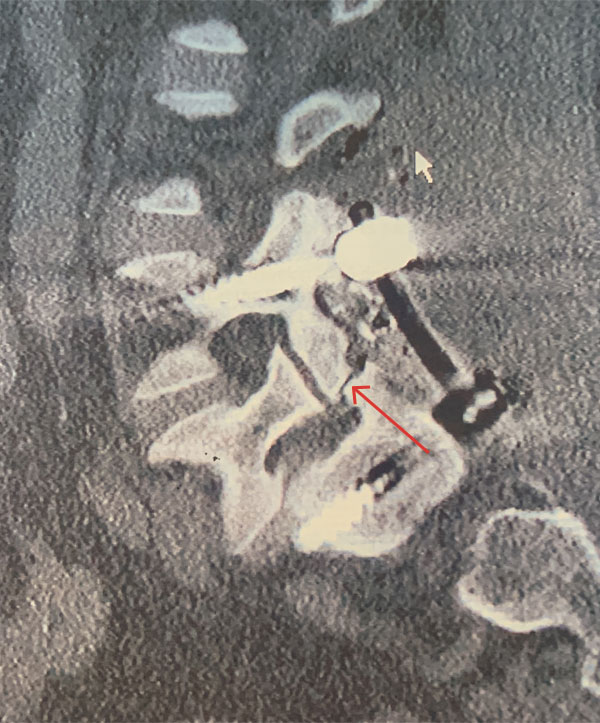

The patient underwent a decompressive laminectomy from L4-S1 with decompression of the L5 nerve roots and instrumented L4-S1 fusion (Figs. 2 and 3). Intraoperatively she had a very loose L5 lamina and had thickened degenerative ligamentous material severely flattening the L5 nerve roots at the level of the lysis defect. The patient tolerated surgery well with significant relief of back and leg pain.

Figure 3 – Sagittal CT image showing post placement of posterior segmental fusion L4-S1 construct. Note pars deflect of L5 (arrow).